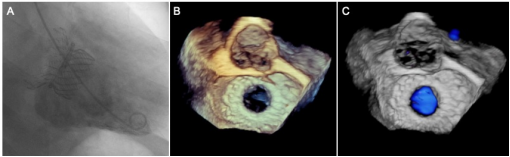

术后即刻造影和超声结果

左图:造影结果提示瓣膜工作良好,二尖瓣无反流;中图和右图:三维超声提示瓣膜工作良好,二尖瓣无反流。